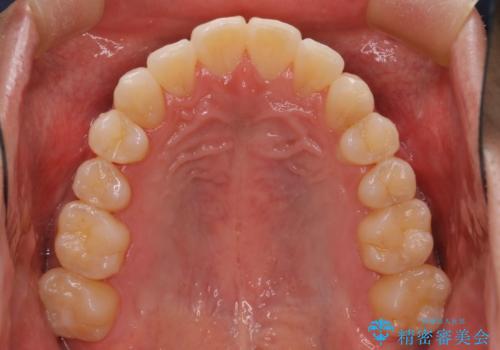

初診時の歯並びの状態としては、上下ともに前歯部の中等度のがたつきがあり、上の前歯が重なっている状態でした。

また元々下の前歯は1本少なく、歯の本数が少ないことを前提とした矯正治療を行いました。

抜歯は必要なく、マウスピース矯正にて治療を行っています。

見た目、嚙み合わせ及び、治療期間や施術内容に大変ご満足いただきました。